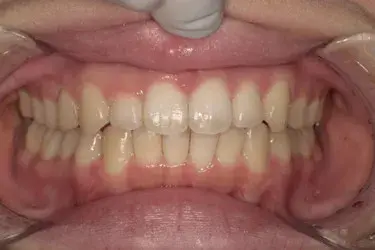

治療期間 4カ月

治療費 23.1万円(月額1,925円~)

※上顎前歯部、下顎前歯部の叢生をマウスピース型矯正装置で改善したケース。矯正治療上のリスクとして、治療中の虫歯、歯根吸収、歯肉炎 ・歯周炎の発生などが考えられる。